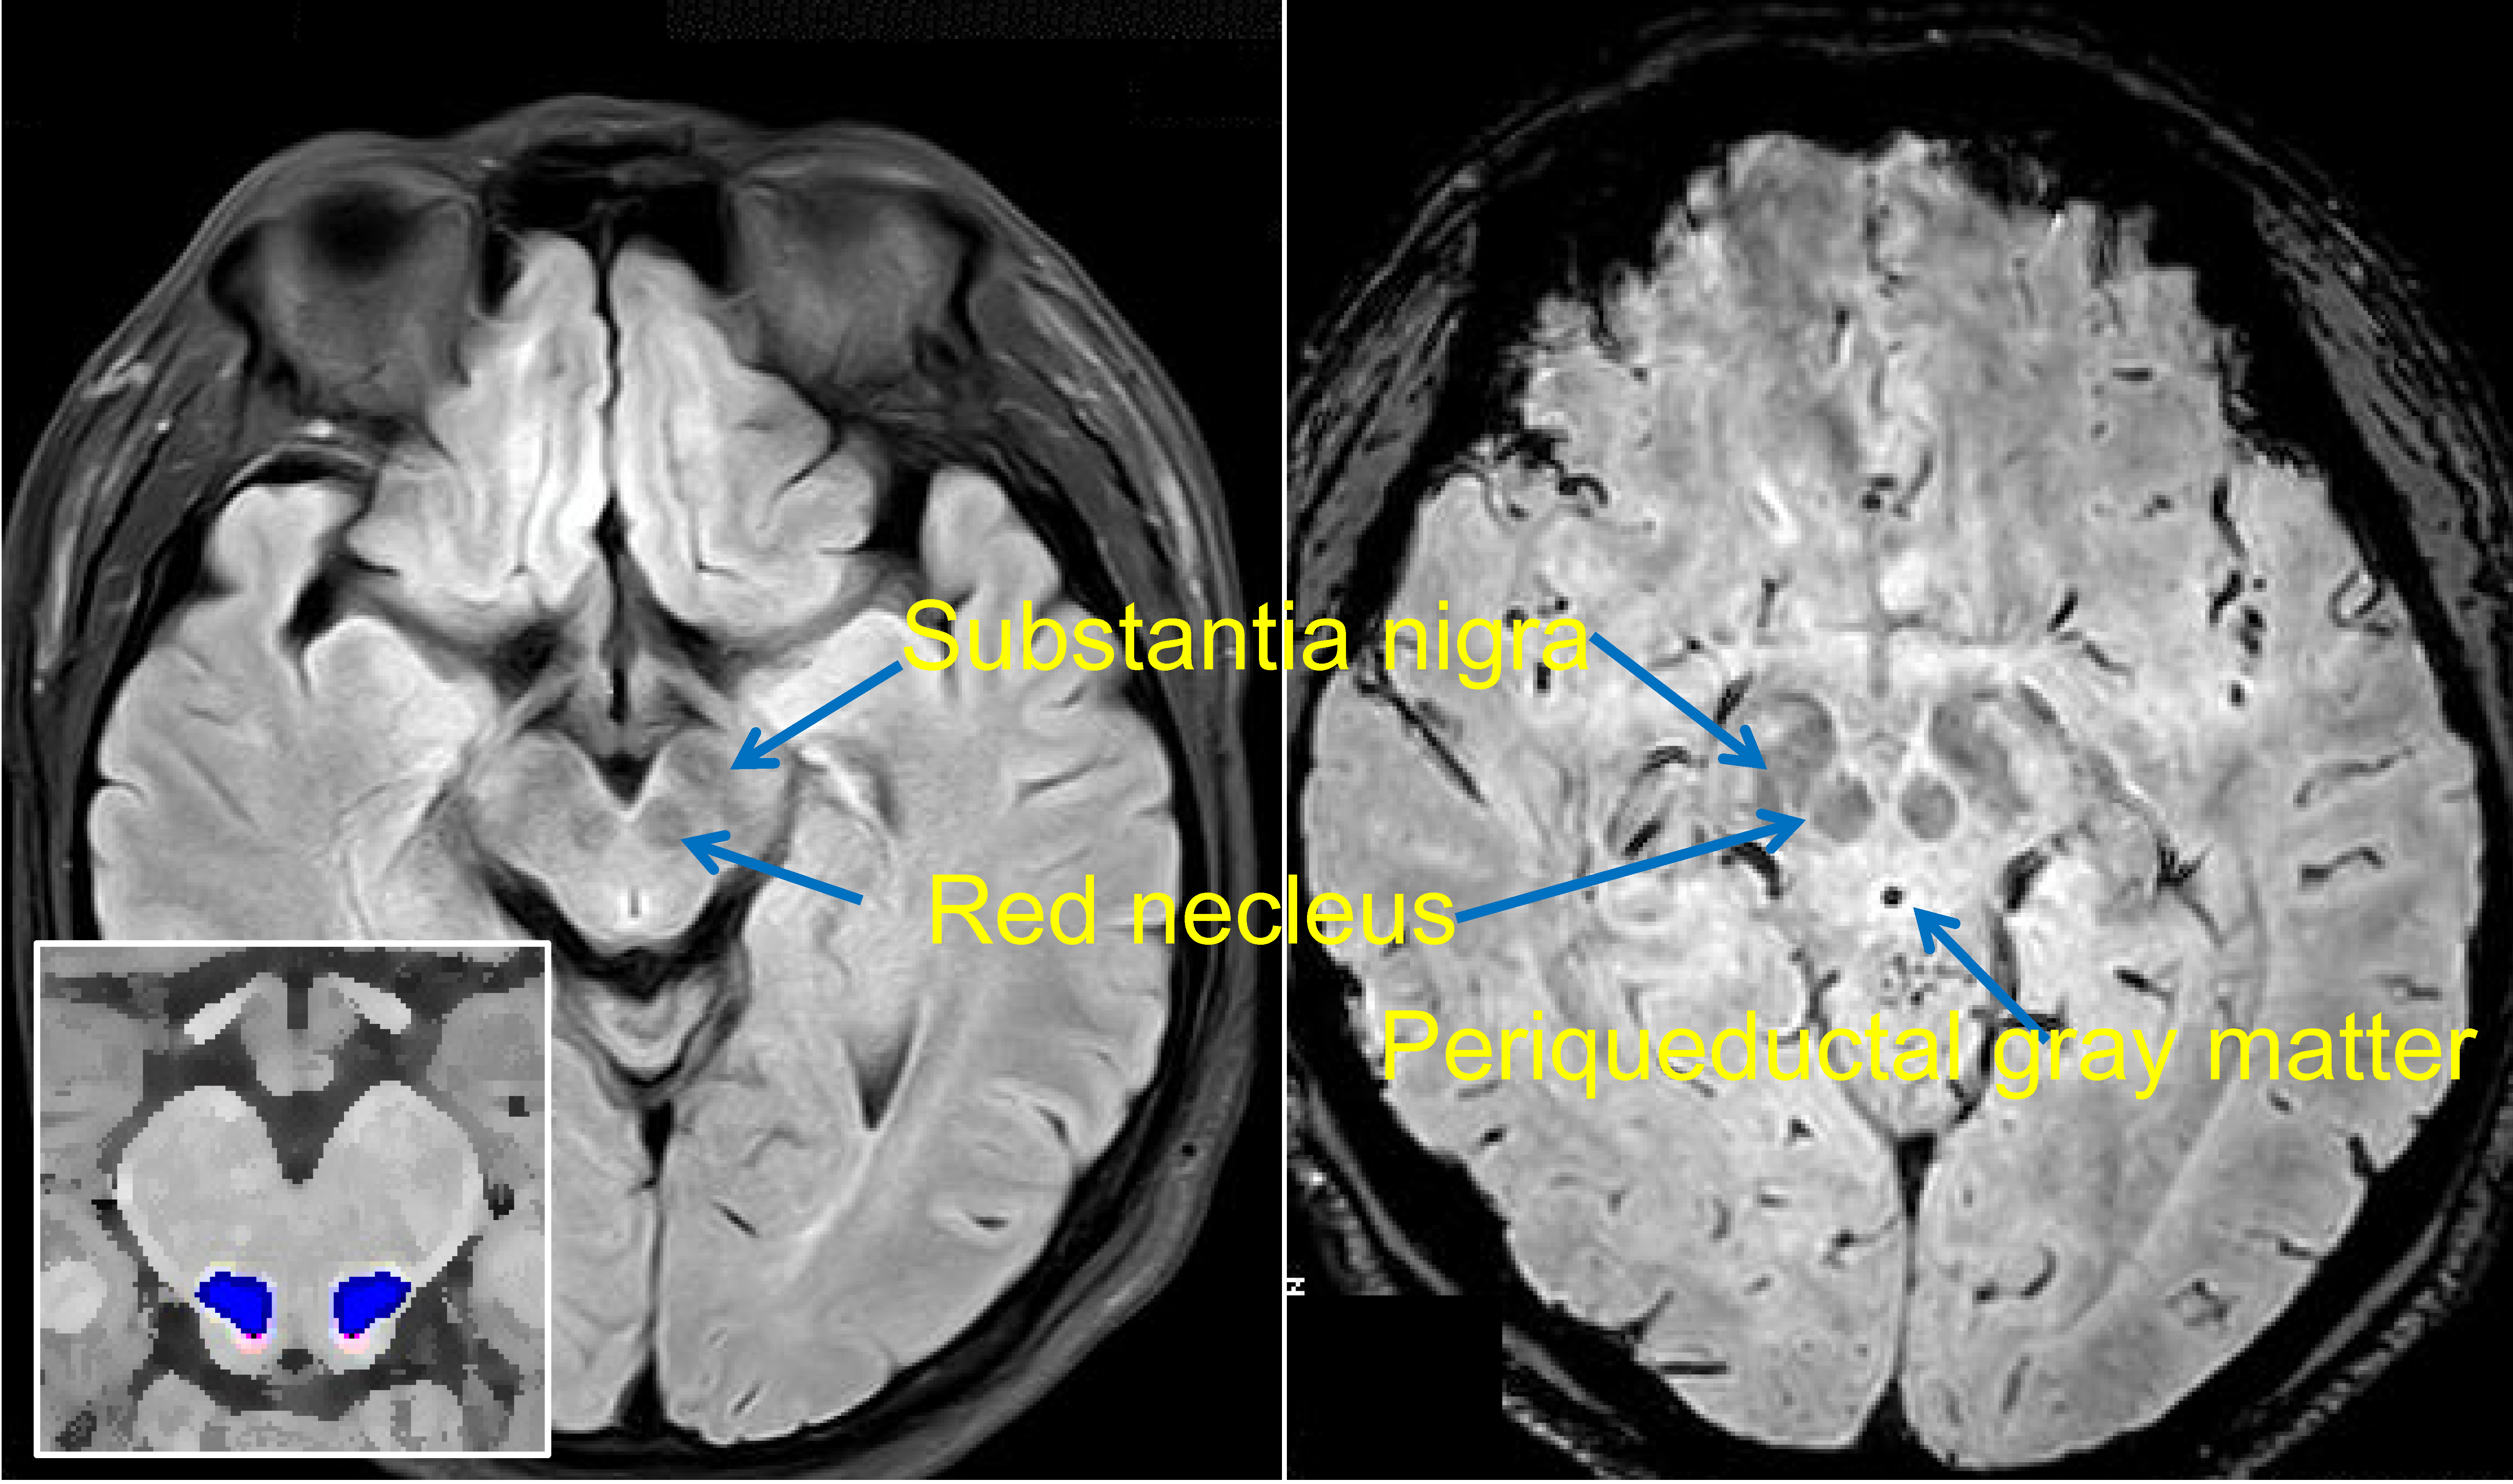

.of the deep cerebellar nuclei in the monkey, with observations on the brainstem projections of the dorsal column nuclei. Cranial nerve nuclei red nucleus substantia nigra. Neurological lesion identification motor (corticospinal pathway) localises the lesion to the contralateral medial brainstem. 4 more scenarios for peter gates brainstem rule of 4. Assessment of traumatic brain injury assessment. 2 ˝open book concept˝ (suggestion of the name by domina petric, md; Be the first to ask a question about stereotaxic atlas of the human brainstem and. A lateral view (right side) of the brainstem relative to. Brainstem special somatic sensory nuclei mediate hearing and positional equilibrium. This brief video tutorial discusses some foundational principals for describing and locating cranial nerve nuclei (motor and sensory) in the brainstem. Assessment of traumatic brain injury online course: Related online courses on physioplus. Inspired with leonard 10 trigeminal complex of the brainstem is general sensory nucleus complex.